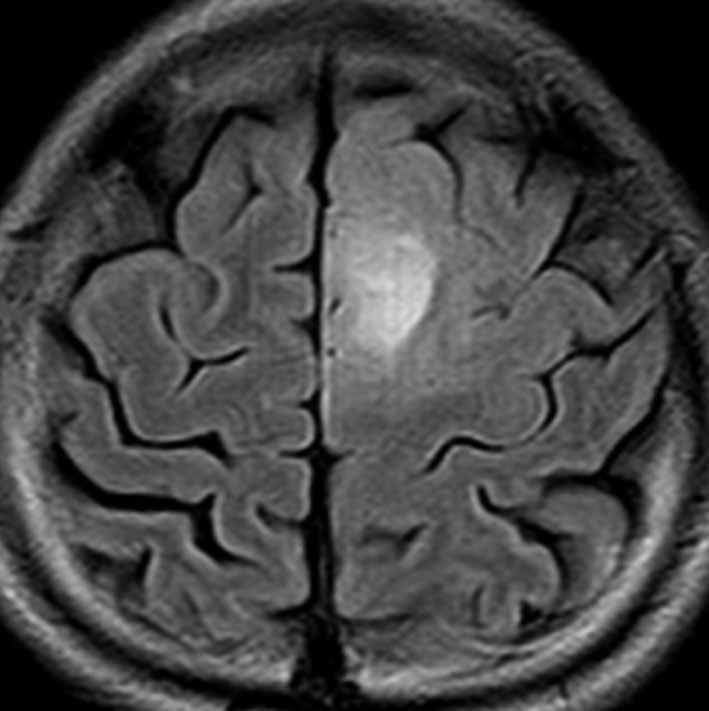

高齢者に発生したグリオーマです。左はガドリニウム増強MRIといいます。腫瘍の周囲が白く縁取られるように見えます。でも,右側のT2強調画像では,白く滲む部分が周囲に広がっています。

グレード3(かつての退形成性星細胞腫)かグレード4(膠芽腫),おそらく膠芽腫と「予想」できる画像です。確実ではないのですが,この予想は治療計画の上で重要なものです。